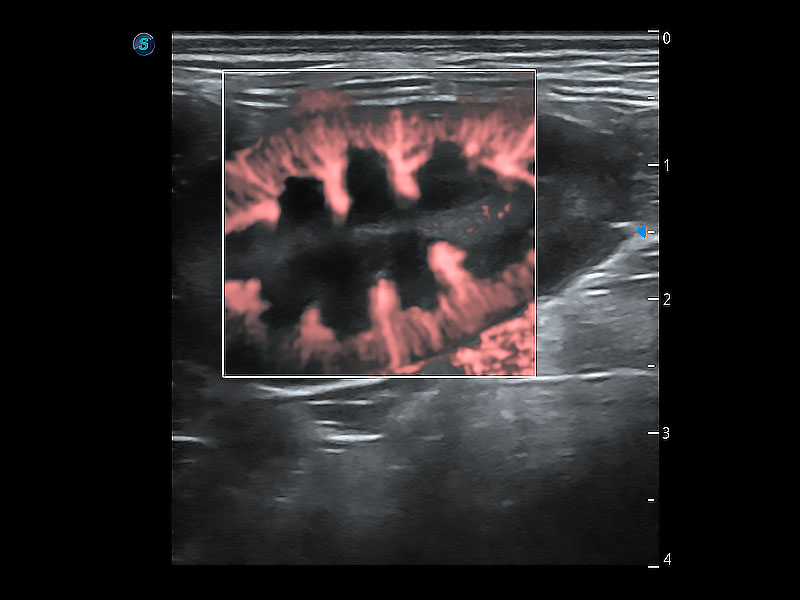

在传统二维血流成像的基础上,呈现血流的立体感,具有动感的生命力之美。即便是微小的血管也能轻松应对,提高了血流的视觉敏感性。

非线性融合造影成像充分利用谐波和基波信号,为难以观察的血流进行增强显像。可用于线阵、凸阵、微凸阵、相控阵探头。